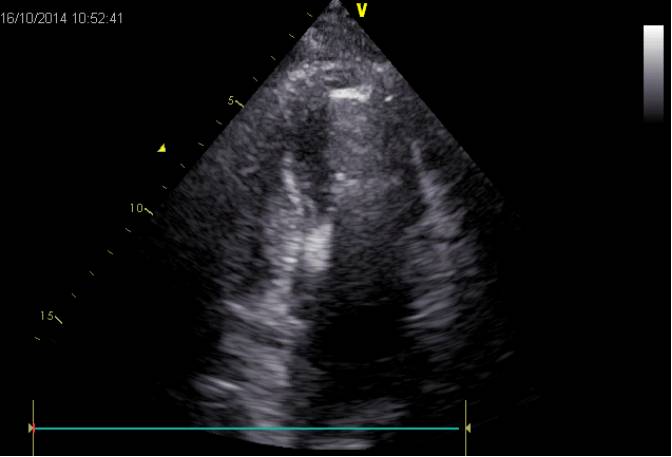

术前心超:

室间隔及心尖部收缩运动减弱;

心尖部室壁瘤形成;

左室舒张末期内径5.7cm,LVEF为35%;

轻度二尖瓣返流;

左房增大。

手术过程B超确认: